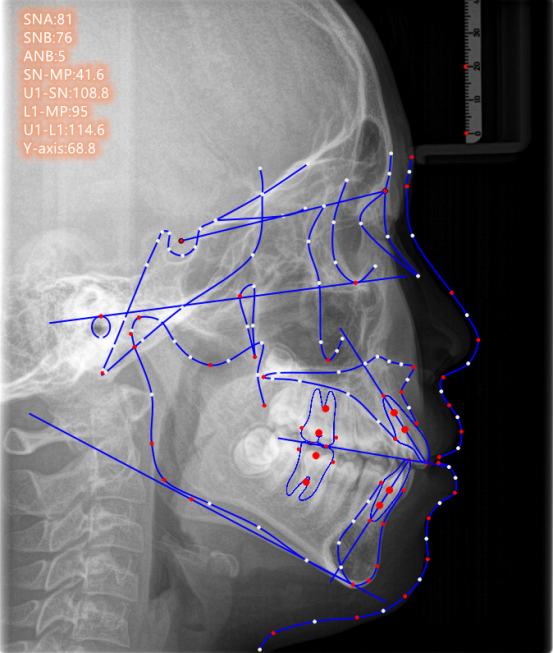

X线头颅侧位片

可以让美学正畸医生了解到牙颌颅面的发育情况,将诊断从表面观察,深入到对整个骨骼的判断,做到精准定位、测量、制定矫治计划。